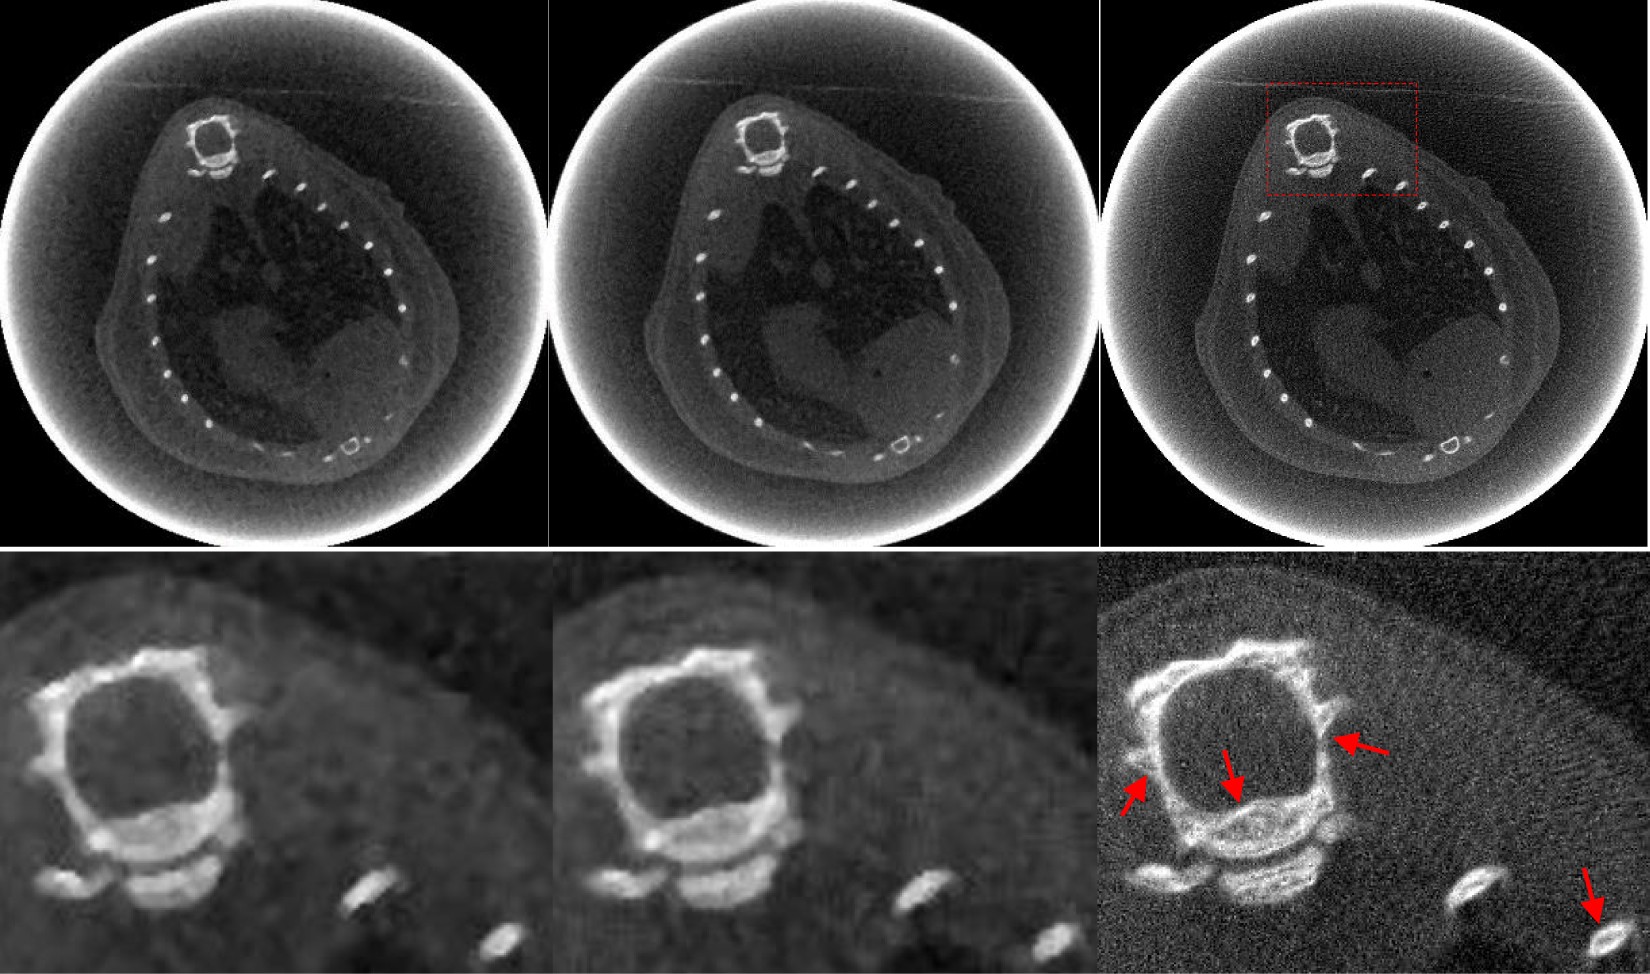

Figure 8

The anesthetized mouse data reconstructions from 225 views by different methods. From left to right, the images of the first row are the results obtained using FBP, PWLS-TV and PWLS-TV-FR method. The images of the second row are the partial enlarged view of the first row.